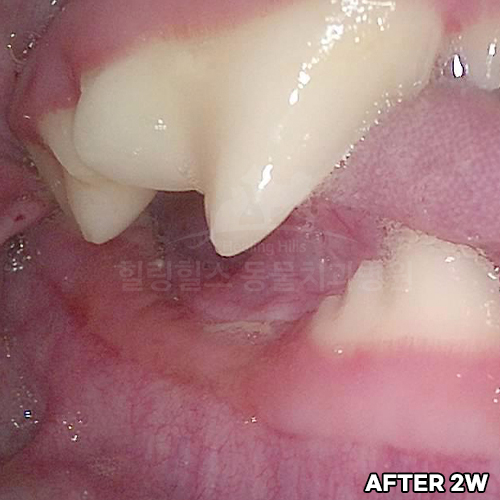

[최소침습적 발치 후 2주 경과]

샘플